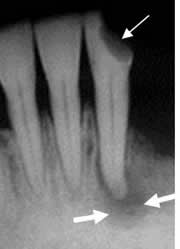

Fig 51 B. Osteitis periapical.

A y B: Rx periapical. Aumento del espacio periapical, por enfermedad periodontal. Los bordes son escleróticos, por evolución crónica. En B se aprecia aumento de la densidad en la cresta alveolar, por osteitis esclerosante.